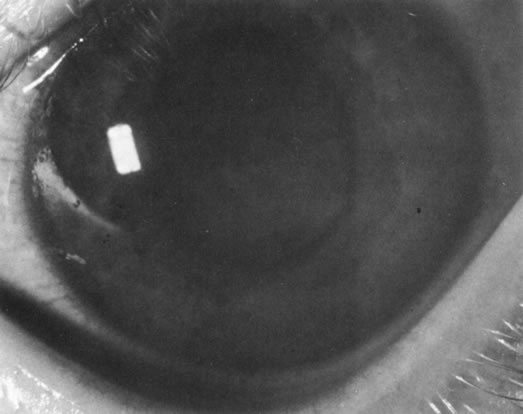

In addition to producing media opacity, inflammation, and cataract, uveal melanomas can also produce other signs that may lead to the incorrect diagnosis of uveitis. Anterior melanomas, especially those that involve the ciliary body, often produce dilated episcleral vessels (sentinel vessels) that occasionally have been misdiagnosed as scleritis (Fig. 6).

Iris melanomas can produce anterior chamber cell and flare, and if the tumor is located in the extreme iris periphery, it may be missed during a cursory examination. Iris melanomas, especially those in a circumferential or ring configuration, are often difficult to diagnose and may simulate either an anterior uveitis or glaucoma.16 Newer, higher-megahertz (high-frequency) ultrasound equipment is better for imaging anterior uveal tumors (Fig. 7).